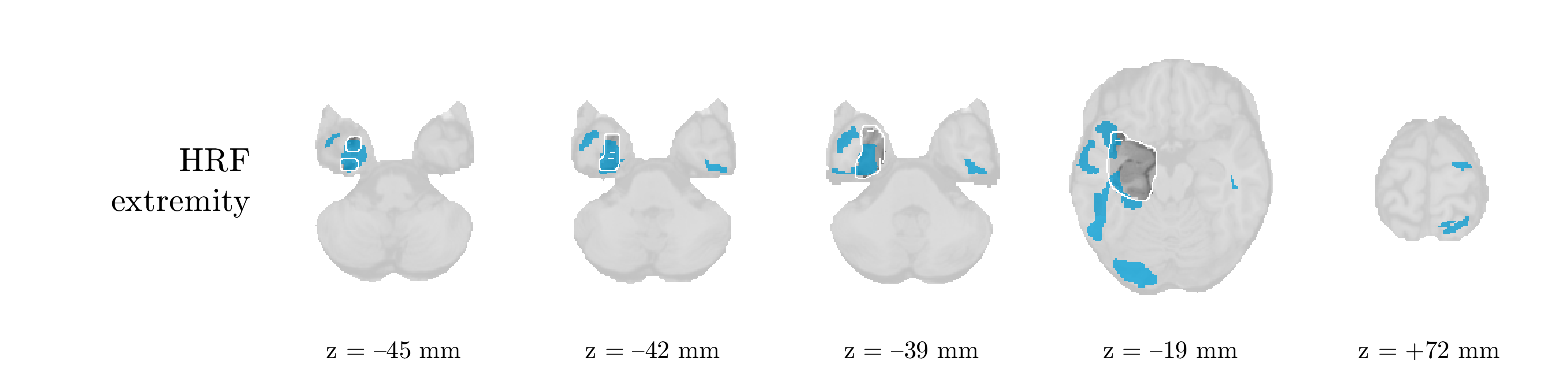

We analyze the solution with sources. Figure 1 shows the EEG signatures and HRF waveforms. One of the sources is highly correlated to the MWF reference (in grey), which was already known from Table B.3. This IED-related source had a typical low-frequency spectrum, which is expected for the typical spike-and-wave interictal discharges. The topography is relatively diffuse, although the highest amplitudes are mostly in the left hemisphere. This is in accordance with the lateralization of ictal onset zone (left temporal lobe, cfr. Table 1). There are some noteworthy observations to be made about some of the other components. The fourth has an unusually sharp spectrum, is mainly localized on two nonadjacent center electrodes, and is sustained for a single period of many seconds Hence, this component likely captured an artifact (of yet unknown origin), although we spotted no large-amplitude changes in the EEG itself. Similarly, the third source is only present at one frontal electrode, and exists in a frequency range above 20 Hz. It might represent a muscle artifact, e.g., due to frowning or twitching of some muscles in the forehead. The HRFs of all ROIs are shown in Figure 1(b). Two of the basis functions seem to have converged to a very similar waveform, which is an unfortunate possibility if two initial HRFs are too close to the same local optimum in their respective parameters. This reduces the expressive power of the basis set, which is clearly visible, since many ROIs have a nearly identical HRF. One of the twenty ROIs with the highest-entropy HRF overlapped the IOZ, although clearly this HRF (bold line) is not among the most dissimilar waveforms for this patient. This is also visible in Figure 2: both the HRF entropy and extremity maps show a small overlap with the delineated IOZ. Despite the good correspondence in the EEG domain, no significant (de)activation of the IED-component is found inside the IOZ.

We analyze the solution with sources, and show the results in Figure 3 and 4. As for patient 1, we found a source which is strongly correlated to the MWF envelope, and which had a mostly low-frequency behavior characteristic for spikes. The topography is mostly uninformative, and does not clearly correspond to the patient’s clinical data. The third source is mostly present at both sides of the head, is very sparsely active in time, and has a high-frequency content: this is most likely an artifact due to the neck muscles. Again, there is one of the highest-entropy HRFs which belongs to a ROI in the IOZ. Now, the waveform is clearly resolved from the other HRFs, through the strong initial dip (before 0 seconds). Such a dip is sometimes observed in HRFs, but its underlying physiological mechanism is not yet fully understood. It is possible that this dip reflects altered vascular autoregulation near the IOZ (cfr. the explanation in the Section 1 of the main text), or a rapid depletion in oxygen due to IED generation (before the IED becomes visible on the EEG). Figure 4 furthermore shows that the IED-related component is significantly active in parts of the IOZ, and deactive in others. As mentioned earlier, this deactivation may or may not be due to errors in sign correction. Interestingly, the ROI with the high alteration in neurovascular coupling is distinct from both the activated and deactivated ROIs.

We analyzed the solution with sources, and show the results in Figure 5 and 6. There is one source which is mostly correlated to the reference (but not extremely, see also Table B.3). This source had a right-temporal focus, conform the diagnosis in Table 1. The second source illustrates the phenomenon of an erroneous sign exchange between the spatial and spectral profiles. Also one of the HRFs has a negative polarity, which is a failure of the sign correction procedure (in this case, because there is exceptionally no positive overshoot). However, the HRF variability metrics are still interpretable, and indeed two ROIs among the ones with the highest-entropy HRFs overlap with the IOZ. The IED component is significantly active in a tiny portion of the IOZ (cfr. Figure 6). The second source is significantly active in symmetrical parts of the parietal lobe. Given its ongoing fluctuation over time, we hypothesize that this source captures a resting state network (RSN).

We analyze the solution with sources, and show the results in Figure 7 and 8. There is a clear IED-related component, with a very high correlation to the MWF reference, a typical spectrum, and an anterior-temporal focus, which corresponds very well to the patient’s diagnosis (cfr. Table 1). The fifth source seems present at only one channel, and has spectral harmonic at Hz and Hz. One of these peaks is reminiscent of the fourth component in patient 1. As Figure 8 shows, the HRF entropy and extremity prove to be strong biomarkers for the IOZ in this case, and also the significant IED activation and deactivation allow correct localization. In Figure 7, it is clear that some HRFs may still have the wrong sign, which means that the interpretation of ‘active’ and ‘deactivated’ is flipped in those ROIs. Hence, regions of significant deactivation are in fact significantly activated. The fourth source had a significant overlap with the auditory RSN, and its spectrum reveals activity in the band.

We analyze the solution with sources, and show the results in Figure 9 and 10. One source is strongly correlated to the MWF, while the other source is likely an artifact, given its very sparse temporal profile. Both sources coincide at one high-amplitude peak, by which we infer that this is probably an artifactual period in the signal. Indeed, when inspecting the original EEG signals, we found high-frequency muscle artifacts at these times. This source also had no significant activation in its spatial map, which corroborates its non-neuronal origin. The IED-related source had a broader spectrum than most other cases, and an uninformative topography. None of the ROIs with high-entropy HRFs is located in the IOZ. The pseudo t-map provides correct localization of the IOZ, however.

We analyze the solution with sources, and show the results in Figure 11 and 12. We found a clear IED-related component, with a characteristic spectrum and a topography which is backed up by the patient’s diagnosis (left anterior-temporal IOZ). The fourth source has a very similar topography and spectrum to the fifth source in patient 5. One HRF inside the IOZ had a high-entropy, and is distinguishable from the others by its very sluggish waveform, i.e., it is smeared out in time, with no sharp over- or undershoot. Also the pseudo t-map provided an accurate localization of the IOZ. Notably, in this patient, the extremity metric misses the deviating HRF in the IOZ (while the entropy metric picks it up). The second source overlapped with the frontal part of the default mode network (DMN), and is active in the and low bands.

We analyze the solution with sources, and show the results in Figure 13 and 14. We found two components which had correlated time courses. At the time of the peaks, we found higher-amplitude events in the EEG with dubious origin, hence they may or may not be artifacts. One of both components is more strongly correlated to the MWF, and its activation is concordant with the IOZ. The second component shows high overlap with the sensorimotor network. For this patient, none of the IOZ’s ROIs had extreme values of either HRF metric.

We analyze the solution with sources, and show the results in Figure 15 and 16. In this patient, there is only a moderate correlation of a component with the MWF reference time course. This component’s topography (left occipital) agrees with the clinical description, however. The HRF extremity (and not the entropy) is high in a small part of the IOZ. Both the significant IED activation and deactivation allow correct localization as well. The second source seemingly captured high-frequency oscillatory activity in the sensorimotor network, similar to the previous patient.

We analyze the solution with sources, and show the results in Figure 17 and 18. The IED-related source had a high correlation with the MWF reference, but an odd bimodal spectrum. Its EEG topography is very consistent with the clinical description. Both HRF extremity and entropy are useful biomarkers for the IOZ. The IED activation and deactivation maps each had a very small overlap with the IOZ. The second source is temporally sparse and captures high-frequency EEG variations, which we identified as muscle artifacts.

We analyze the solution with sources, and show the results in Figure 19 and 20. Again we observe an IED-related source and a seemingly artifactual source with a spectral peak near 34 Hz. Many of the high-entropy HRFs are highly noncausal, and are associated to ROIs inside the IOZ. Hence, with both HRF metrics, the highest-scoring ROIs provides good localization of the HRF. While there are no significantly active ROIs in the IOZ, there are several significantly deactivated ROIs, which may indicate that the sign standardization was not done flawlessly (cfr. also some of the negative-peaking HRFs for patient 10). Surprisingly, the second source had one significantly active ROI, which overlaps with the IOZ, but which did not match its EEG topography. Hence, the nature of this source remains ambiguous.